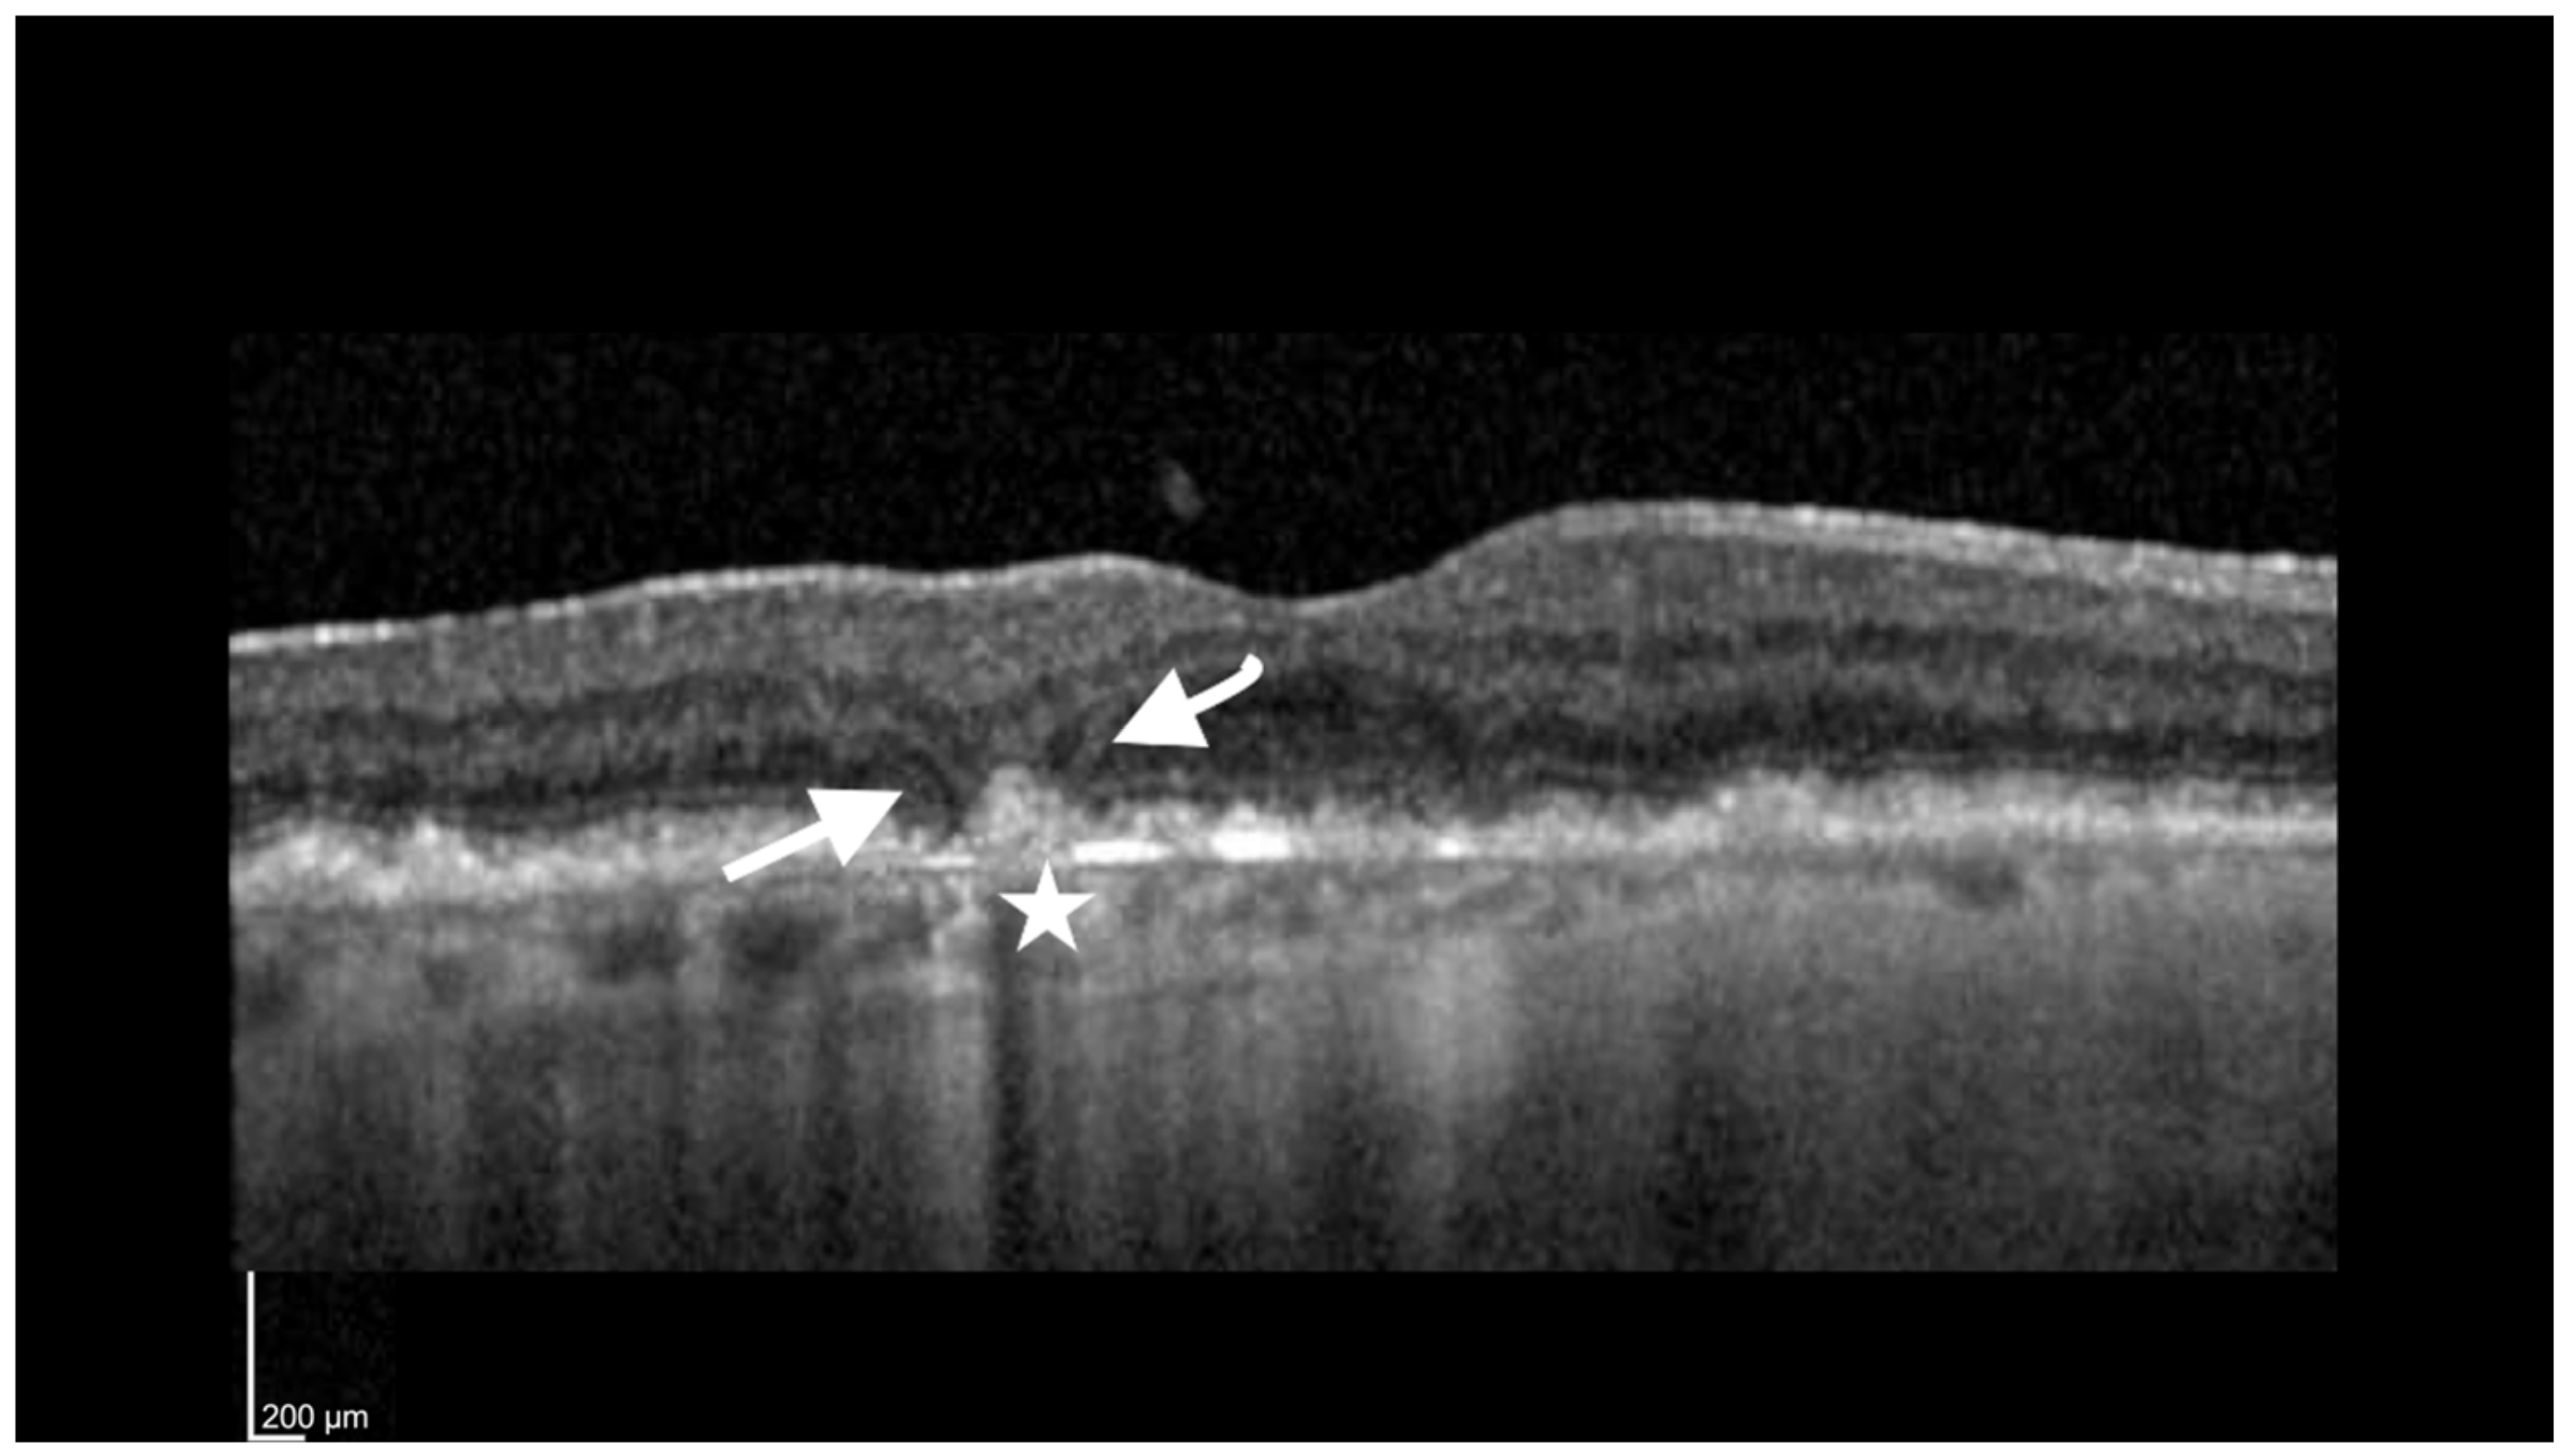

- Sato, T.; Kishi, S.; Watanabe, G.; Matsumoto, H.; Mukai, R. Tomographic features of branching vascular networks in polypoidal choroidal vasculopathy. Retina 2007, 27, 589–594. [Google Scholar] [CrossRef]

- Shi, Y.; Motulsky, E.H.; Goldhardt, R.; Zohar, Y.; Thulliez, M.; Feuer, W.; Gregor, G.; Rosenfeld, P.J. Predictive Value of the OCT Double-Layer Sign for Identifying Subclinical Neovascularization in Age-Related Macular Degeneration. Ophthalmol. Retin. 2019, 3, 211–219. [Google Scholar] [CrossRef]

- Narita, C.; Wu, Z.; Rosenfeld, P.J.; Yang, J.; Lyu, C.; Caruso, E.; McGuinness, M.; Guymer, R.H. Structural OCT Signs Suggestive of Subclinical Nonexudative Macular Neovascularization in Eyes with Large Drusen. Ophthalmology 2020, 127, 637–647. [Google Scholar] [CrossRef]